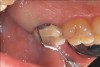

Fig 6. Pre- (Fig 5) and post- (Fig 6) DGV procedure. Note the 7-mm pocket distal to tooth No. 15 before treatment and normal probing depth after treatment. It would have been easier for the restorative dentist to place this crown with increased tooth structure if the tuberosity tissue had been removed previously.

Figure 6

The clinician must determine which of these two harvest techniques should be utilized. Each has its advantages in different situations. For non-wide (buccal-palatal dimension) tuberosities, the DGV technique offers less tissue loss. For wide tuberosities, which are greater than 4 mm in width buccal-lingually and have more CT, the DW technique may be advantageous, as the flap can be approximated and closed with sutures, and this potentially may be more comfortable for the patient. Either technique adequately removes the excess tissue and reduces the pocket. The DGV approach provides a faster tissue harvest and a greater amount of tissue (Figure 5 and Figure 6).

Because the tuberosity tissue has denser CT than the palate tissue, it is easier to filet into multiple grafts. Additionally, the epithelial layer is very thin. This poses a distinct advantage for the DGV technique over the DW. If the DW technique is used, more CT will be left with the flap and less CT will be available for the graft. Some or all of the epithelial layer may be retained if it is desired to keep keratinized tissue retained in the graft. From the ease of harvesting to maximizing the amount of CT, the authors prefer the DGV technique over the DW; however, in some circumstances, such as with wide tuberosities, the DW approach may be more advantageous.